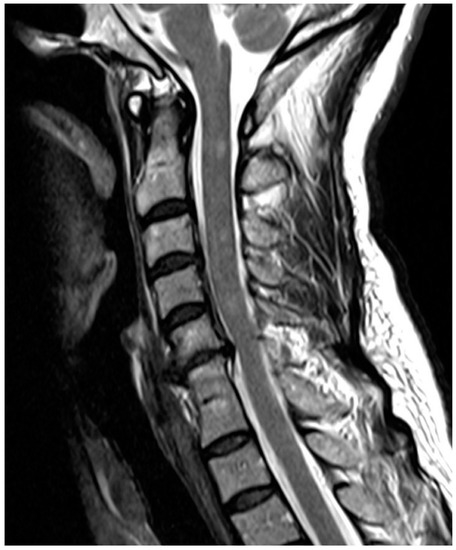

Are Congenital Cervical Block Vertebrae a Risk Factor for Adjacent Segment Disease? A Retrospective Cross-Sectional CT and MR Imaging Study

Adjacent segment disease (ASDI) is a well-described complication of spinal fusion surgery that may ultimately lead to spinal stenosis and repeated surgical intervention. Although congenital block vertebrae also present with degenerative changes in the adjacent segments, this has not yet been systematically investigated. The aim of this study was to assess the presence and degree of ASDI in congenital cervical block vertebrae. Methods: A total of 51 patients with congenital vertebral fusion in one cervical segment were analysed in this IRB-approved retrospective cross-sectional study using available CT/MR imaging. Exclusion criteria were prior spinal surgery and the presence of additional hereditary abnormalities. We assessed the severity of degenerative changes using a sum score. The sum score for adjacent and non-adjacent segments was then divided by the highest possible degeneration score, which resulted in a ratio of severity for adjacent and remaining segments (ranging from 0 to 1). Results: Overall, 35 of 51 patients (68.6%) showed evidence of ASDI, and 34 of 51 patients (66.7%) also showed degenerative changes in the remaining segments. The severity score was significantly higher (p = 0.025) in the segments adjacent to the congenital block vertebrae (mean value 0.307) compared to the non-adjacent segments (mean value 0.188). Conclusions: Our results suggest that ASDI is also caused by congenital block vertebrae of the cervical spine. Full article

Figure 1